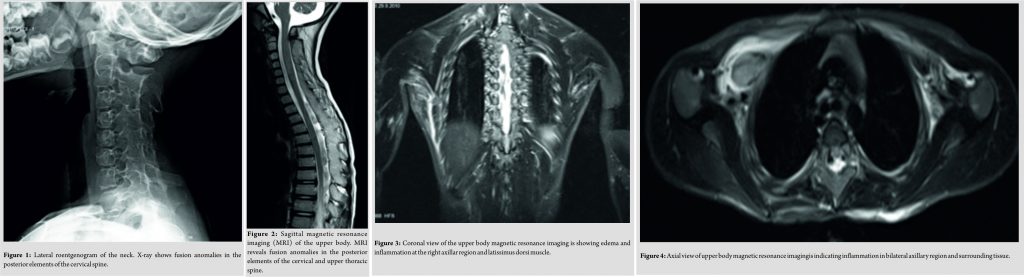

A 5-year old boy had a 2-weeks history of a fall at school. At the time of presentation, physical examination revealed a diffuse elastic soft mass behind his neck and below his right scapula. His shoulder abduction was limited to 90° bilaterally. He had also limited cervical movements in lateral rotation and flexion. He was unable to put his clothes on by himself. Ultrasound, peripheral blood analysis, and biochemistry parameters were normal. There were no malignancies detected. X-ray and magnetic resonance imaging (MRI) revealed fusion anomalies at the posterior elements of cervical and upper thoracic spine (Fig. 1,2).

All immunological and tumor markers were negative. Lymphoscintigraphywas normal. HLAB27 was the only positive immunologic parameter. In 3 weeks, significant loss of abduction in shoulder joints was noted bilaterally. MRI revealed enhanced edema at bilateral axillary region (Fig. 3, 4).